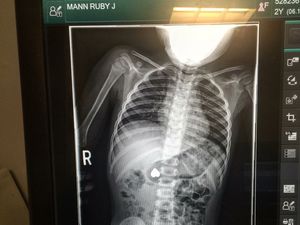

Vaper Melawan! Ramai-ramai, Pengguna Vape Pamer Foto Rontgen Paru-paru

Pengguna vape atau rokok elektrik bereaksi terhadap isu larangan vape karena alasan kesehatan. Mereka ramai-ramai memamerkan foto rontgen paru-paru.